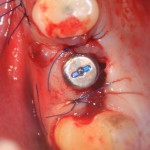

Немедленная имплантация — оптимальное решение в любой клинической ситуации